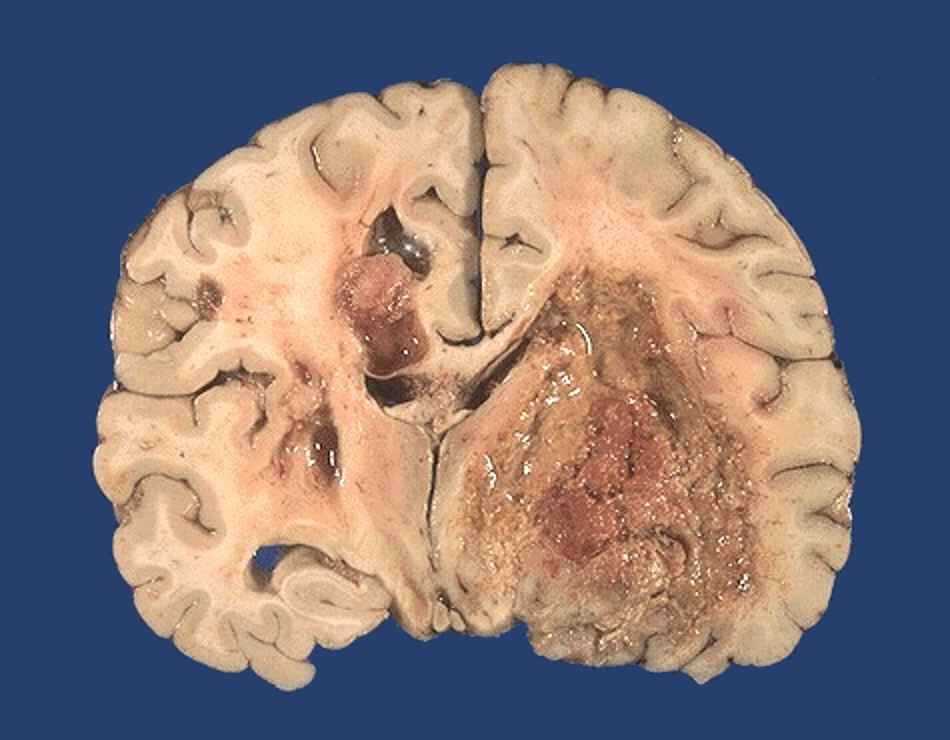

Refer to caption

Figure 2.1: Macroscopic example of glioblastoma. Image taken with kind permission from https://webpath.med.utah.edu/CNSHTML/CNS136.html

Figure 2.1 shows an example of a brain affected by glioblastoma. Note the deep invasive ability of the tumor, evidenced by the tumor foci crossing the midline towards the opposite hemisphere of the largest mass.